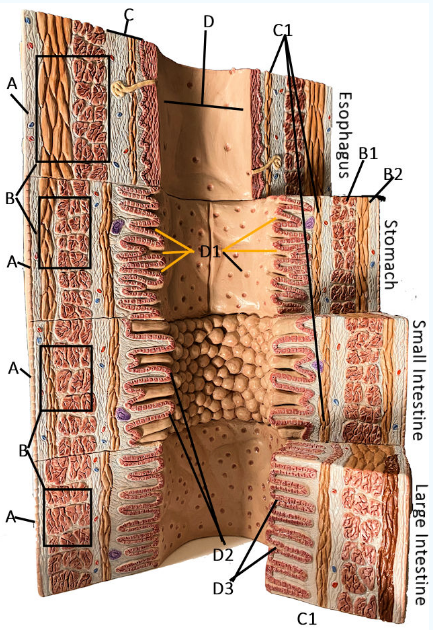

A

Serosa

B Esophagus

Muscularis externa: skeletal, skeletal/smooth, and smooth, circular and longitudinal

B Stomach

Oblique, circular, and longitudinal smooth muscle

B Small intestine

circular and longitudinal smooth muscle

B large intestine

circular and longitudinal smooth muscle

C

Submucosa: areolar and dense connective tissue

D

Lumen

D1

Gastric glands/pits

D2

Villi of small intestine

D3

Intestinal crypts of large intestine